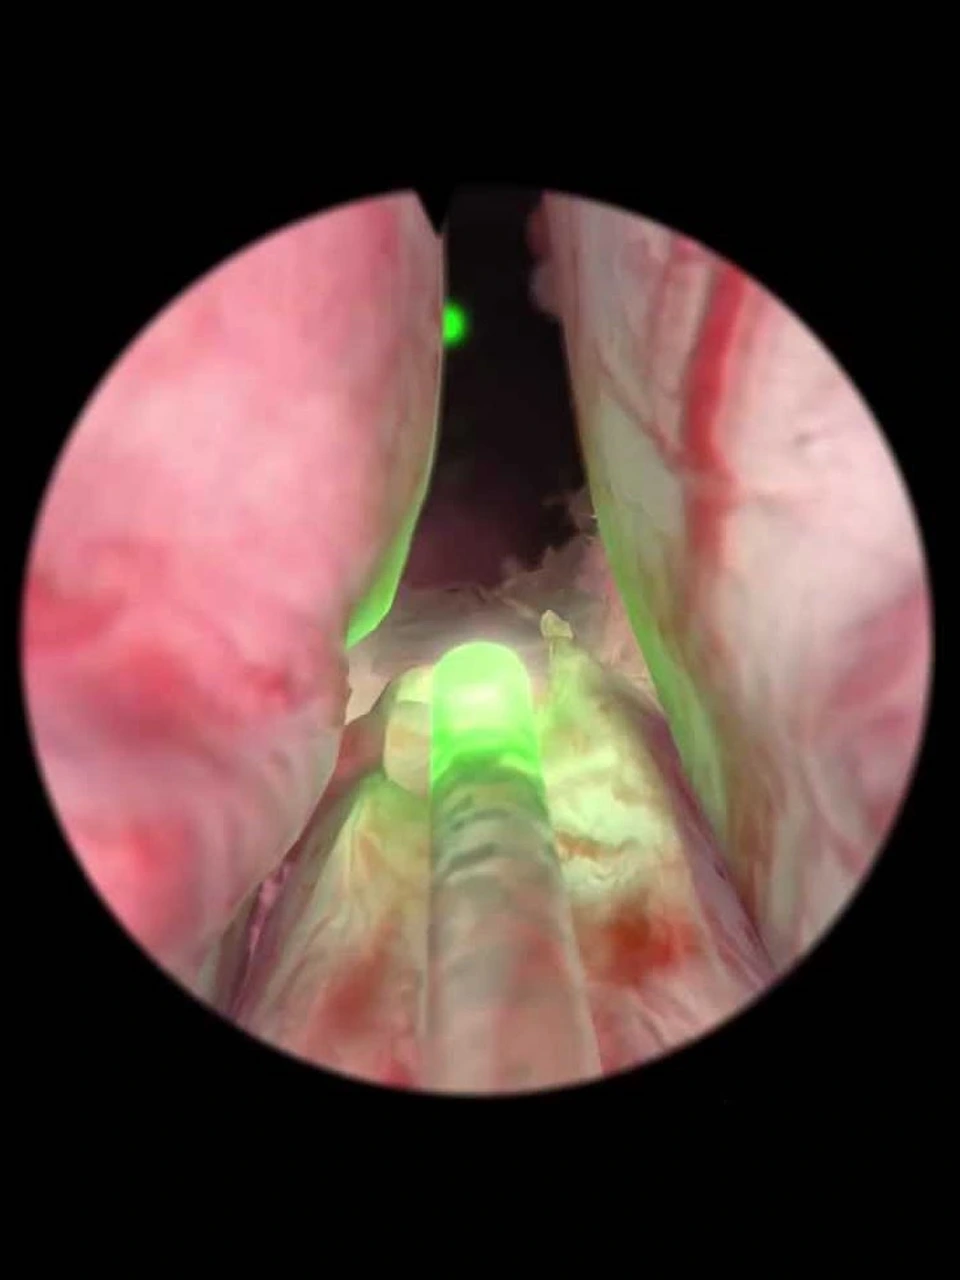

O HoLEP é realizado em três etapas principais. Primeiro, o laser de holmium é utilizado para enuclear (separar) o adenoma prostático da cápsula prostática, preservando a arquitetura normal da próstata. Esta etapa requer habilidade técnica específica e experiência do cirurgião para identificar corretamente os planos anatômicos.

Na segunda etapa, o tecido enucleado é fragmentado (morcellated) em pequenos pedaços através de um equipamento especial chamado morcelador, permitindo sua remoção completa através da uretra. A terceira etapa envolve a hemostasia cuidadosa para controlar qualquer sangramento residual.

O laser de holmium possui características únicas que o tornam ideal para este procedimento. Sua energia é absorvida pela água dos tecidos, criando vaporização precisa com penetração tecidual mínima (apenas 0,4mm), garantindo segurança e precisão. A hemostasia (controle do sangramento) é excelente, reduzindo significativamente o risco de transfusão sanguínea.